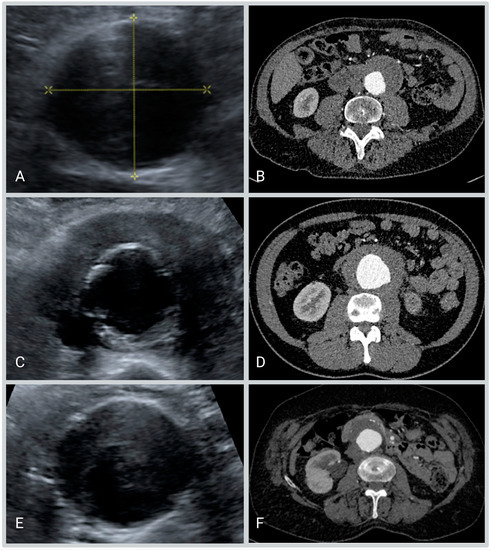

- The maximum anteroposterior diameter of the aorta including the hypo-echogenic layer outside the calcified layer.

- The anteroposterior diameter of the aorta excluding the hypo-echogenic layer (up to the calcified layer)

- The thickness of the hypo-echogenic layer at the anterior site of the aneurysm.